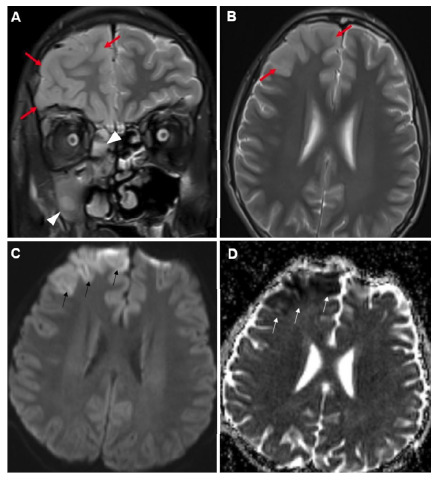

Widespread Encephalitis Following Acute Sinusitis in a Pediatric Patient.